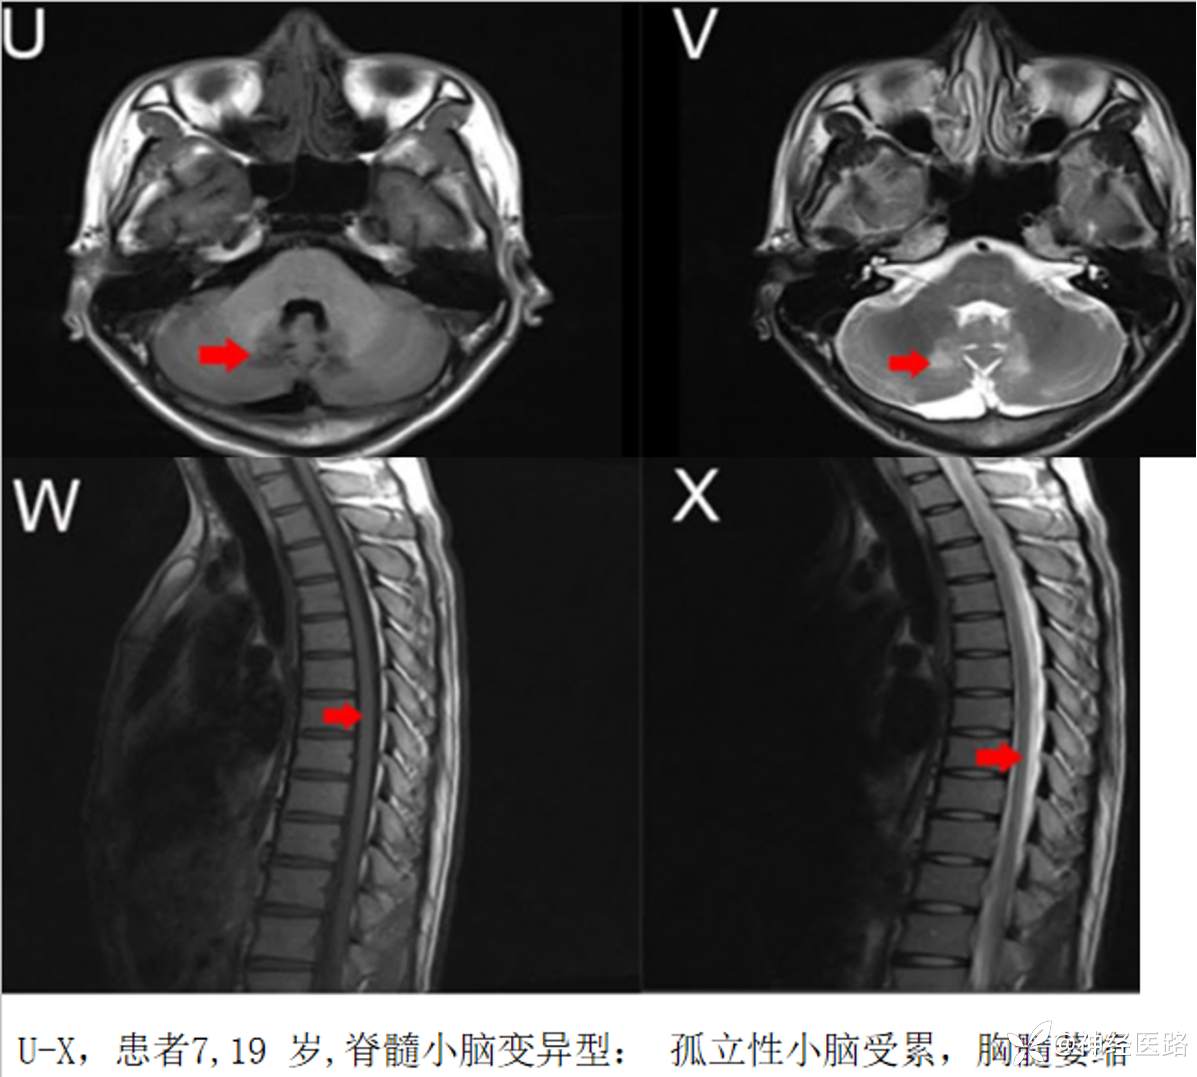

AMN中罕见表型可以脑干和(或)小脑表现为主,命名有多种,包括以脊髓小脑变性为表现的AMN、橄榄桥脑小脑型、小脑型、共济失调型、脊髓小脑型等。

脊髓小脑变异型肾上腺脊髓神经病小脑病变多表现实质内异常信号,而非萎缩。